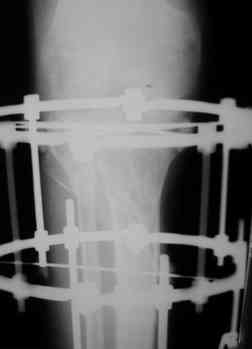

Р-граммы за март и апрель

> Р-граммы за март и апрель

Постараться отрепонировать наружное плато, вероятно с костной пластикой. Фиксация метафизарного перелома пластиной LCP PLT (дорого и локальный статус ноги должен быть соответствующий), если нет - то по Илизарову (заметьте - не спицами и кольцами от аппарата И., а по методу И.).